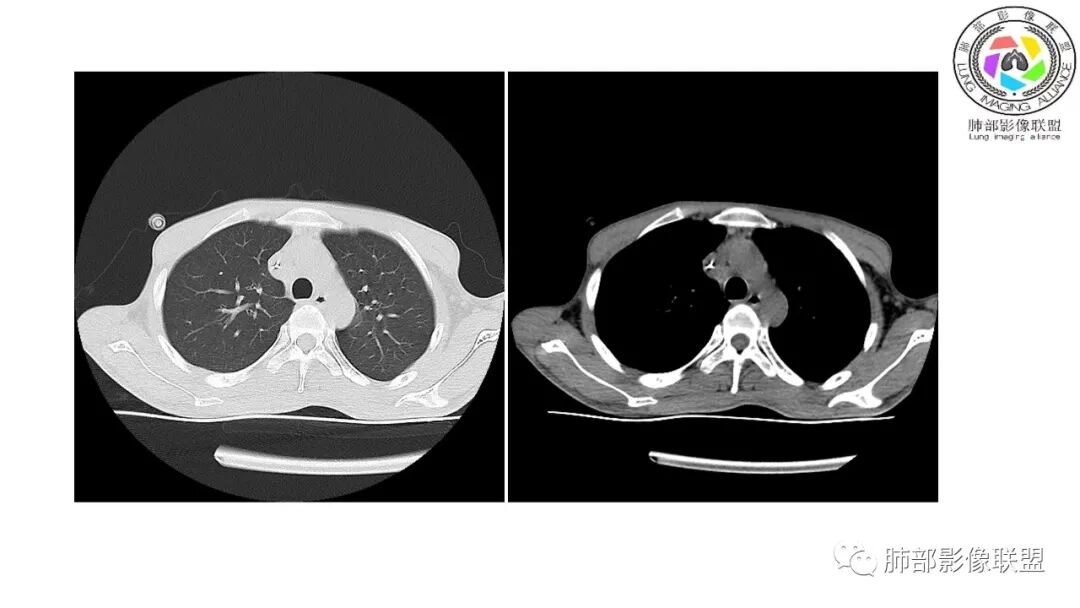

影像与临床:1.青年男性,HlV阳性,颜面部皮疹(未提供皮疹图像)、发热(高热),实验室CRP、PCT高,T-Spot阴性。2.右肺下叶空洞结节,壁厚不均,边界清楚,其内线状影,未见液平及钙化,未见卫星灶,纵隔淋巴结增大,双侧腋窝见增大淋巴结。心腔内低密度提示贫血可能。肝脾影增大,未见结节影及块影。腹膜后见多发增大淋巴结。

综合分析:本例肺部影像学改变并不具有特征性,空洞性病灶须与多种疾病鉴别,但年轻HIV阳性患者,高热,皮疹,肝脾增大,纵隔、腋窝、腹膜后见多发增大淋巴结等都强烈提示马尔尼菲篮状菌感染的可能性。